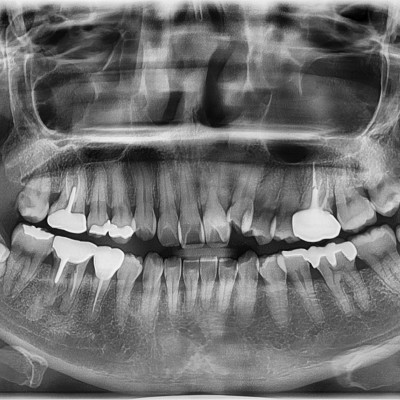

#18,28,38,48 사랑니 발치 N새글 #18,28,38,48 사랑니 발치 구강 외과 전문의가 당일 발치했습니다. --------------------..

작성자 이턱이 작성일 18:00 조회 1